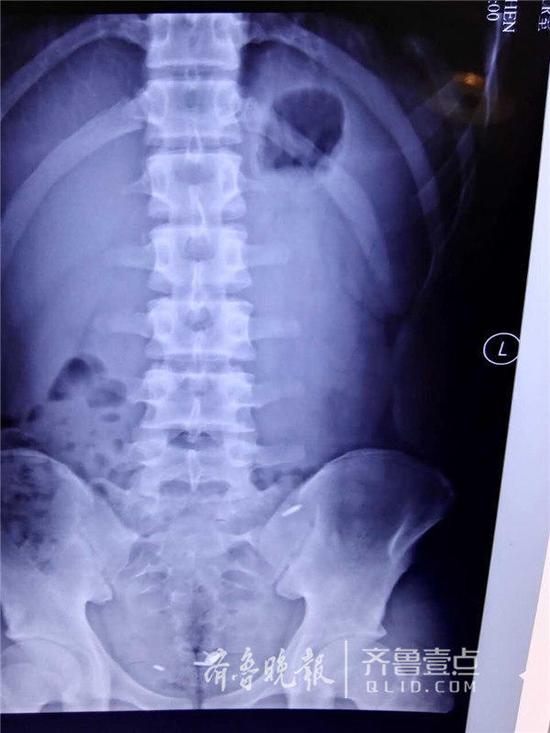

腹中的圆珠笔芯

因与同学打赌,济南一名16岁的少年竟口吞一枚图钉,并将三个圆珠笔芯头从肚脐生生塞入腹腔中。事发后,少年被送至山东大学齐鲁医院急救。医生们经过4个小时的艰难寻找,才通过腹腔镜将三个圆珠笔芯头取出,而那枚图钉也在第二天被幸运地排出体外,整个过程十分惊险。

7日,一名16岁的少年王川(化名)被送到山大齐鲁医院进行抢救,医护人员介绍说,来的时候少年表情轻松,但他的讲述却让所有人都吓了一跳。原来,王川因为跟同学打了一个200块钱的赌,吞下了一枚图钉,后来又把三个圆珠笔芯的头通过肚脐塞到了肚子里。而无论是图钉还是笔芯头,都很尖锐,一旦划破肠道或是腹腔后果不堪设想。

“非常难找。”李鹏宇说,王川年龄还小,为了减少创伤,他们在王川的肚脐和左右腹部各打了一个小孔,然后通过腹腔镜进行探查,但没想到在艰难地找到一个圆珠笔芯头后就再也找不到了。“由于翻找,笔芯头一直在换地方,一会在上面,一会在下面;肠子的大网膜、肠间隙非常多,情况复杂。”术中,一度医生们考虑或许只能通过创伤大的开腹手术将其取出,但考虑到孩子年龄,又坚持了下去。终于,历经了4个小时的艰难寻找,才终于把三个长1厘米左右的笔芯头给取了出来。